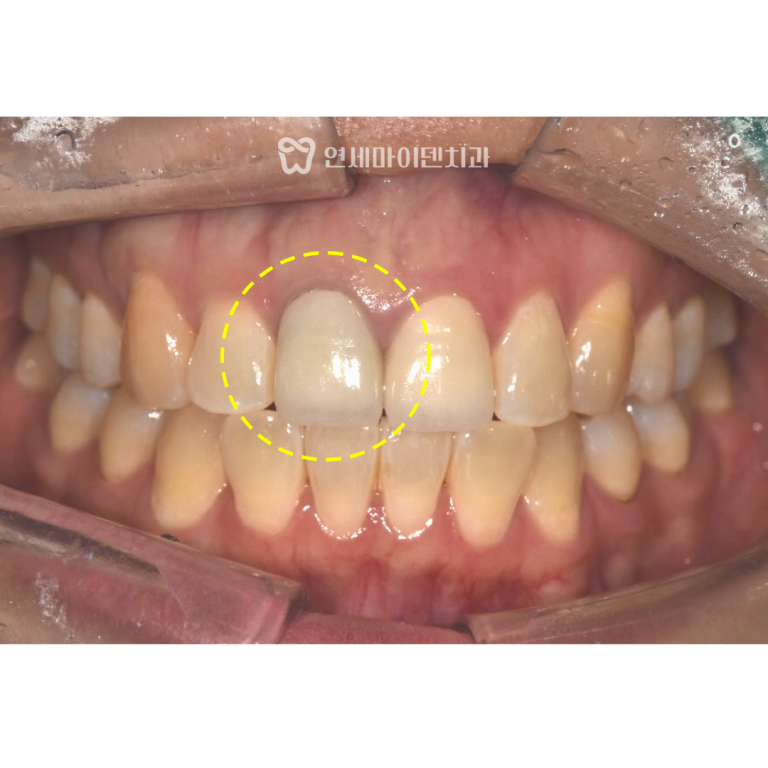

초기 검사에서 엑스레이상

충치나 뚜렷한 염증은 보이지 않았고,

잇몸 상태 역시 비교적 안정적인 모습이었습니다.

육안으로 확인했을 때도

표면이 약간 거칠어 보이는 것 외에는

특별한 이상이 없는 상태였습니다.

그래서 추가적으로

큐레이(Qray) 광선을 이용해

치아 표면을 확인하는 검사를 진행했습니다.

큐레이 검사를 통해

치아 표면에 미세한 금이 간 라인이

명확하게 확인되었습니다.